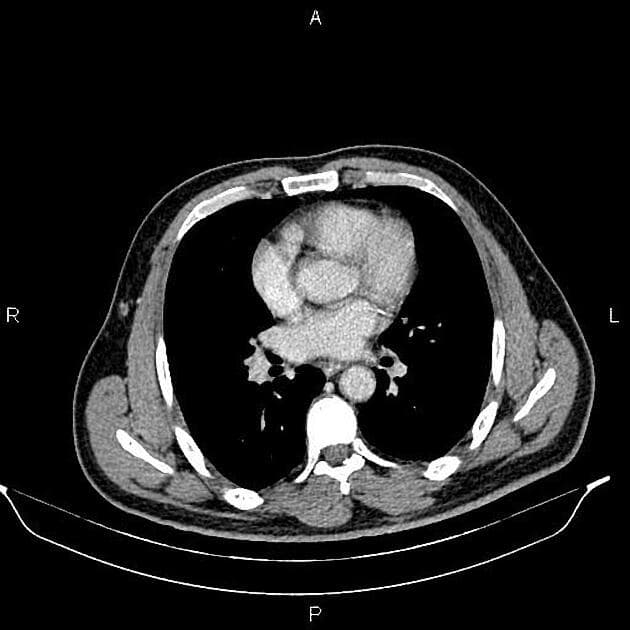

Axial C+ portal venous phase

- Túi mật không thấy do đã cắt bỏ trước đó.

- Một khối dạng đặc kích thước 60 x 55 mm nằm ở phần trung tâm gan. Khối này có tín hiệu thấp trên hình ảnh T1WI và tín hiệu hơi tăng mờ trên T2WI. Sau tiêm thuốc tương phản, khối cho thấy tăng quang viền với hiện tượng ngấm thuốc hướng tâm (centripetal filling). Tĩnh mạch cửa trái bị khối chèn ép.

- Có sáu tổn thương tương tự trong gan, gợi ý di căn (metastases).

- Các ống mật trái giãn nhẹ; ống mật chủ (common bile duct – CBD) không giãn.

- Thấy hình khuyết lấp đầy dạng dải tại tĩnh mạch cửa chính, phù hợp với huyết khối mạn tính (chronic thrombosis).

- Một vài hạch bạch huyết bất thường (lymphadenopathies) ở cửa gan (porta hepatis), đường kính ngắn (SAD) nhỏ hơn 15 mm.

- Một khối giảm tăng quang kích thước 65 x 50 mm, có vôi hóa bên trong, nằm ở phần trung tâm gan.

- Ngoài ra còn sáu khối nhỏ giảm tăng quang khác, kích thước nhỏ hơn 20 mm, rải rác ở nhu mô gan.